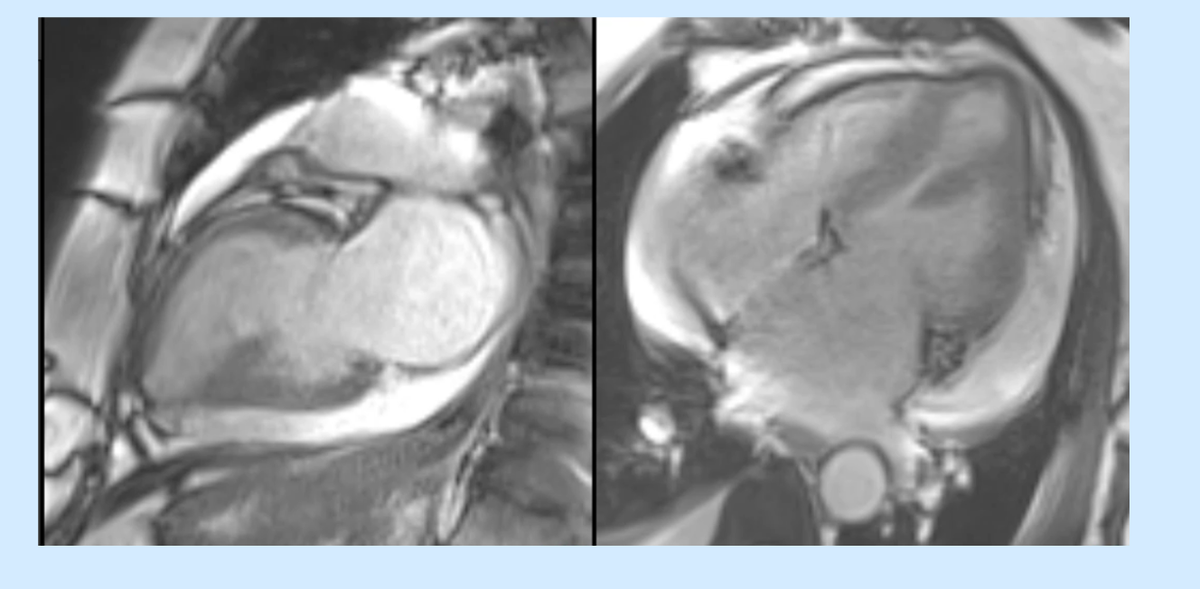

Pericardial and pleural effusion